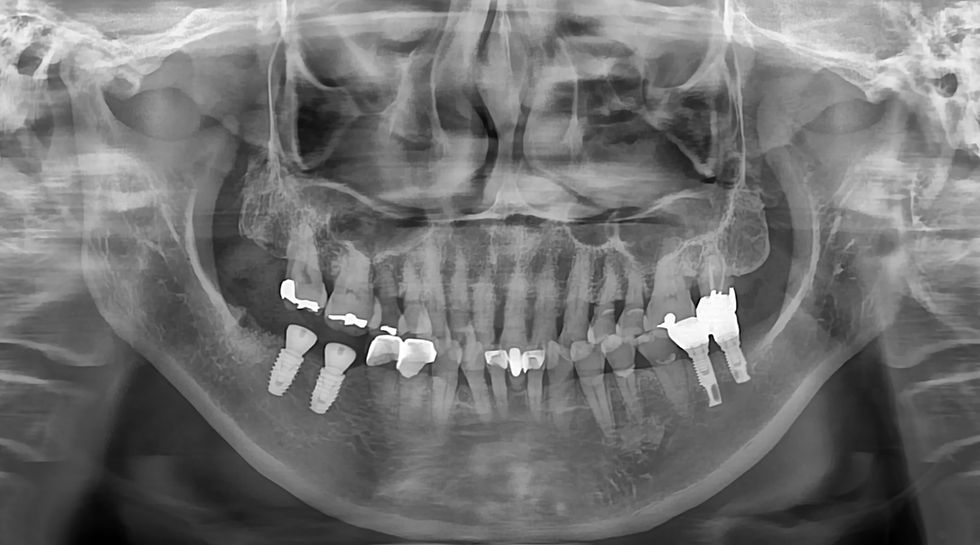

Panoramic radiograph taken after placement of IS-III implants at #46 and #47. Both implants are well positioned with an ideal angulation and parallelism, demonstrating accurate placement.

Annual follow-up was performed through 2024, and the most recent panoramic radiograph confirms stable peri-implant bone levels with no evident bone loss, indicating successful long-term maintenance over the 8-year follow-up period.

This case demonstrates the long-term clinical stability of IS-III implants placed in the mandibular posterior region over an 8-year follow-up period. Both implants achieved high primary stability at the time of placement and maintained stable peri-implant bone levels without signs of pathological bone loss through annual radiographic evaluation.